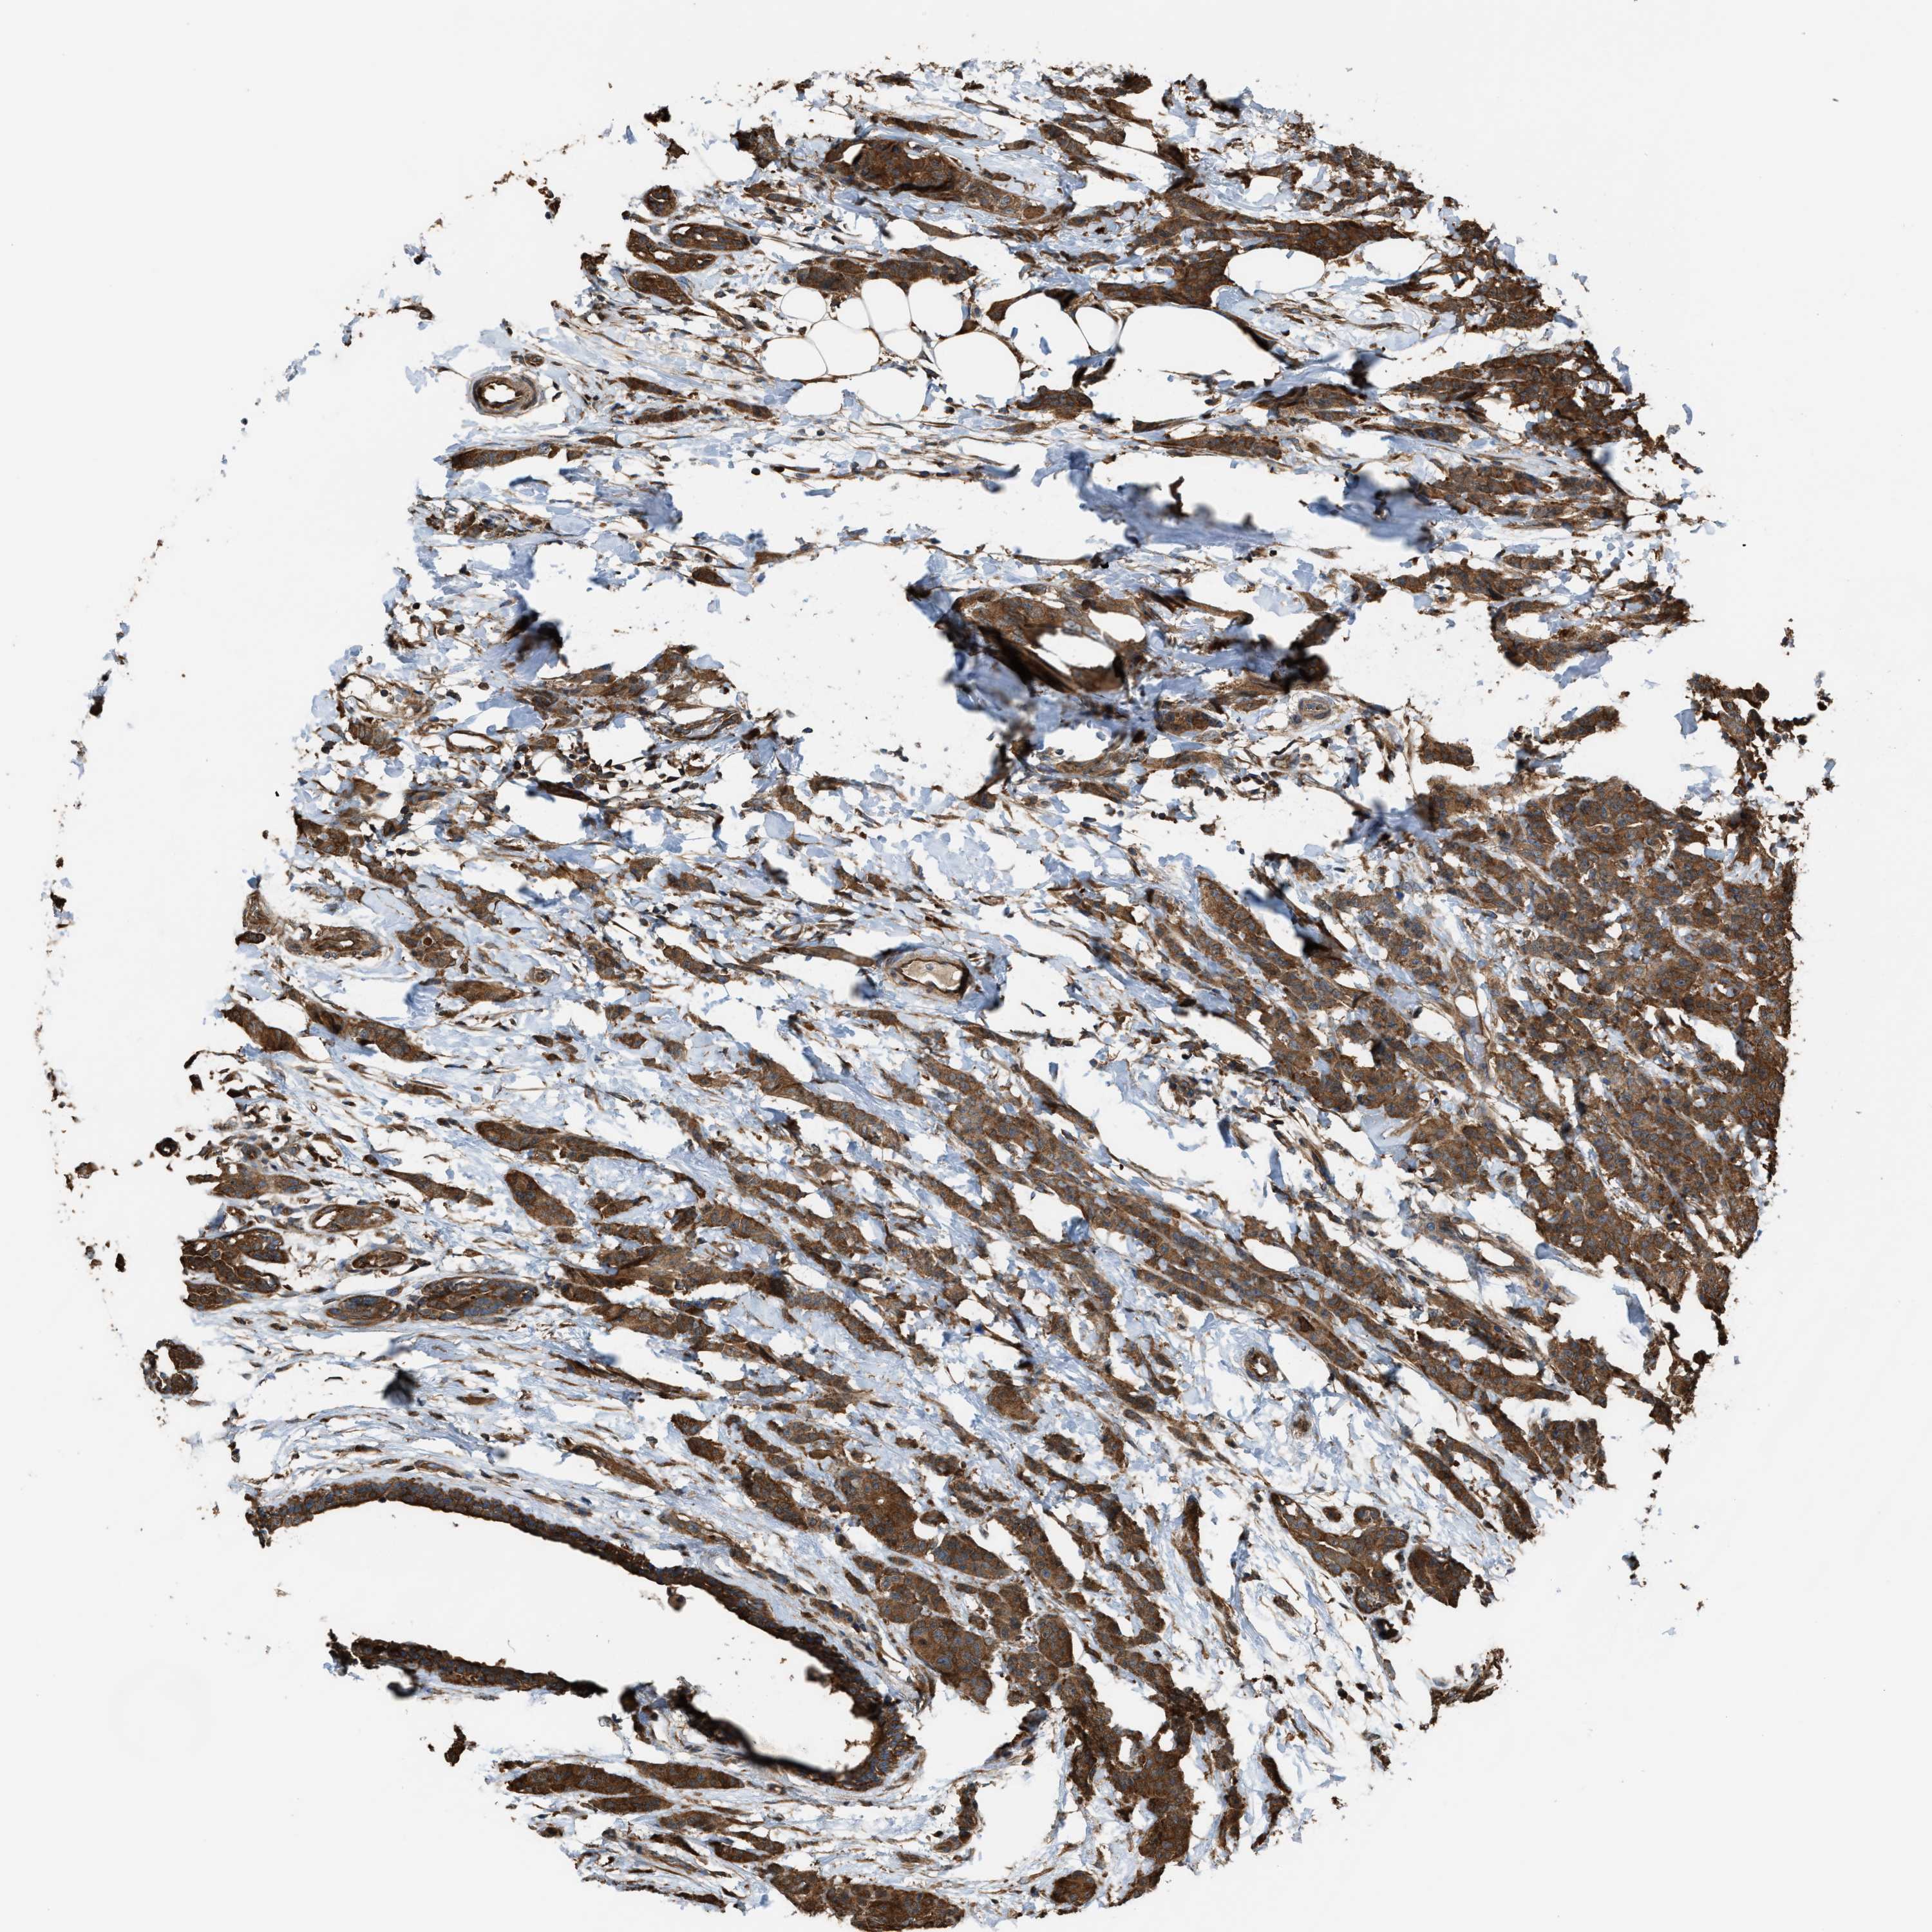

CANCER BREAST CANCER Show tissue menu

BRCA TCGA BRCA VALIDATION PROTEIN EXPRESSION